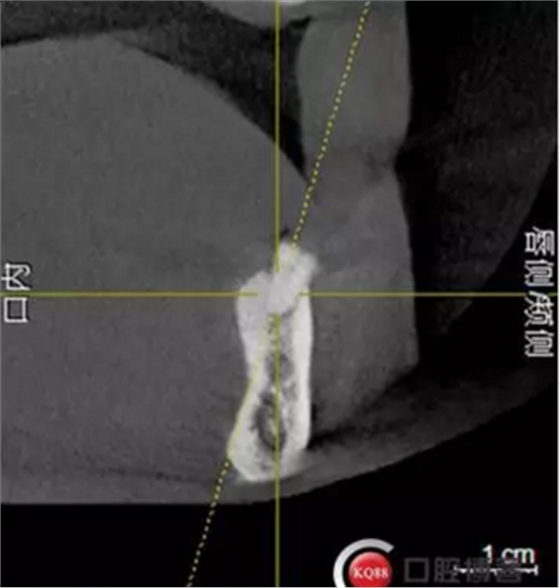

檢查:上頜無(wú)牙頜假牙穩(wěn)定性尚可,下頜3435364243殘根;33殘冠1-2度松動(dòng),其他牙齒缺失;CBCT檢查:下頜牙槽骨前牙區(qū)骨高度足,后牙區(qū)骨高度最低為8mm,骨寬度足。

1)術(shù)前檢查,拍攝臨床照片及CBCT檢查,制取活動(dòng)義齒參考模型,指導(dǎo)后期最終修復(fù)的牙齒排列